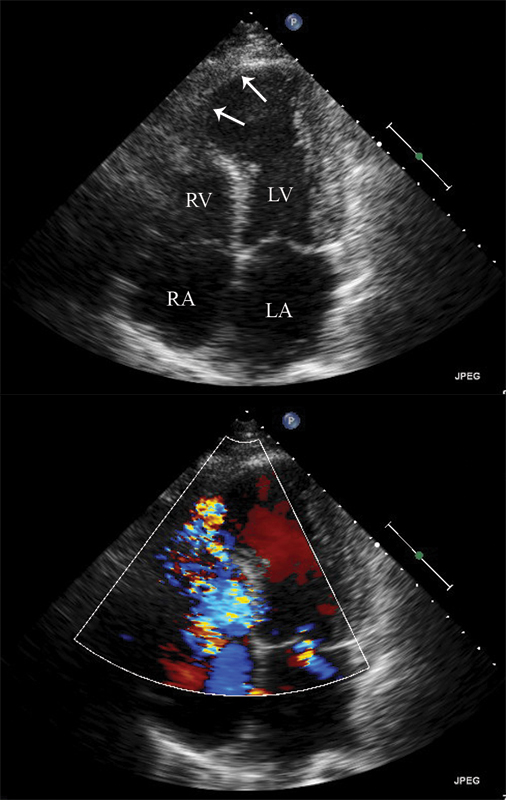

فحوصات تشخيصية لبعض امراض القلب والشرايين التاجية